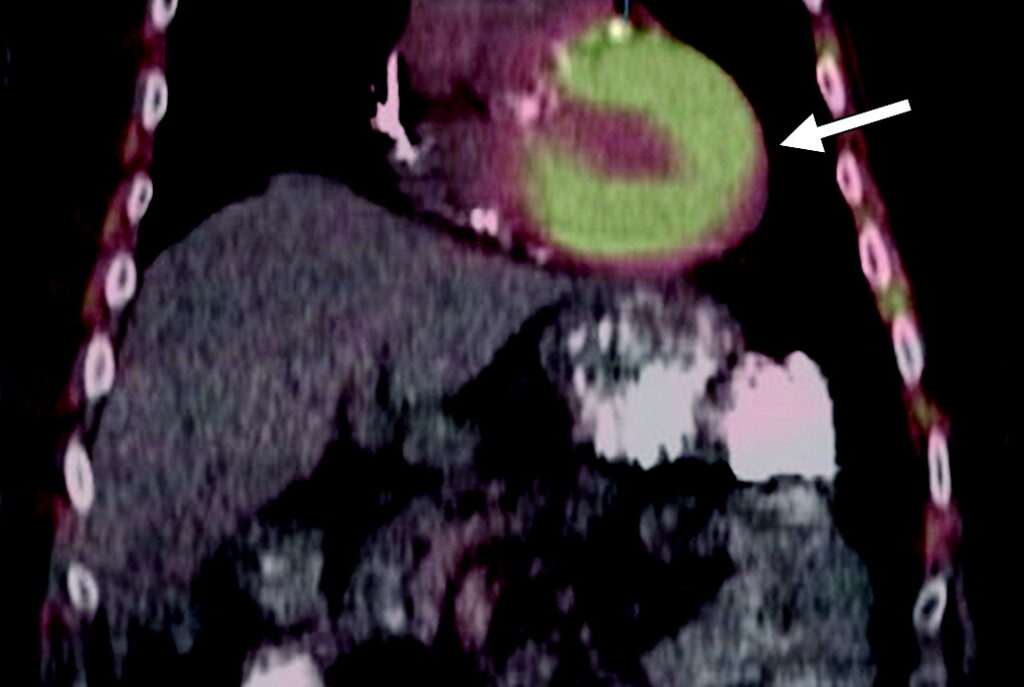

Uomo con tumore alla prostata e presunta amiloidosi cardiaca.

Sia l’acquisizione planare che lo studio tomografico ibrido (SPECT/TC) documentano un’intensa e inequivocabile captazione del radiotracciante osteotropo a livello del muscolo cardiaco. Il pattern di distribuzione globale e diffuso a tutto il miocardio è l’elemento chiave. Questo aspetto permette di escludere altre patologie cardiache che causerebbero una captazione focale o regionale, come l’infarto acuto del miocardio (dove l’accumulo avviene nell’area necrotica), o processi infiammatori come pericardite, sarcoidosi e miocardite.

La ritenzione miocardica dei difosfonati del tecnezio è un segno altamente sensibile e specifico per l’amiloidosi cardiaca, in particolar modo per la forma da accumulo di transtiretina (ATTR). In questo contesto, l’esame eseguito per la patologia oncologica di base si trasforma in uno strumento fondamentale per confermare questa severa condizione sistemica concomitante.